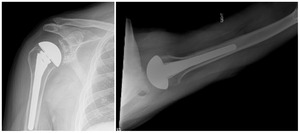

Case one is a 58-year-old male who is an avid golfer with long standing right shoulder pain. Surgical history includes previous Bristow procedure 30 years prior. Current Subjective Shoulder Value (SSV) is 30% and pain is 8/10 at baseline. Active range of motion was 110° of forward flexion, -10° of external rotation and interna rotation to the lateral buttock. Radiographs (Figure 1) and computed topography (CT) scan (Figure 2) show retained implants with loss of joint space, glenoid retroversion, and significant posterior humeral head subluxation. The patient had failed conservative management and was indicated for arthroplasty. Due to significant posterior bone loss and retroversion, an augmented anatomic component was selected for this patient. Radiographs at one year show a well seated glenoid component with restoration of the joint line and a centered humeral head (Figure 3). At five years, SSV had improved to 95% with excellent clinical motion (Figure 4).